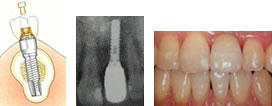

ハイクオリティーインプラントは、インプラント(人工歯根)の形が天然の歯と同じような根の形、その上につく土台も天然歯と同じような白さと硬さ、土台の上に被せる歯(見える部分)も天然歯そのものです。

インプラントの構造と名称

インプラントは、骨に埋め込む「フィクスチャ―」、人工歯を取り付けるためのアバットメント、人工歯の3つで成り立っています。